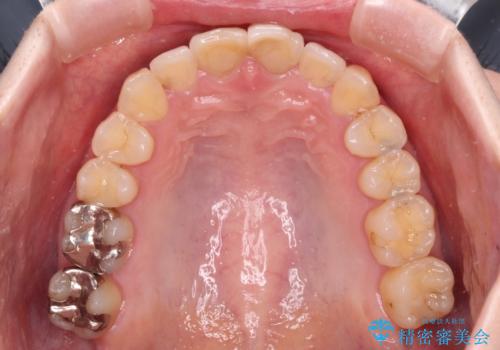

上下前歯のデコボコをきれいに インビザラインによる矯正治療

- 前歯の著しい叢生と前突感を気にして来院された患者様です。

叢生が強いため、事前に前歯をワイヤー矯正で速やかに叢生を解消し、その後はインビザラインにて矯正治療を行うこととしました。

ワイヤー矯正を併用したことで前歯の叢生を速やかに解消することができました。

一方口元の突出感を改善するために時間がかかり、2年超を要しましたが、満足のいく仕上がりとなりました。